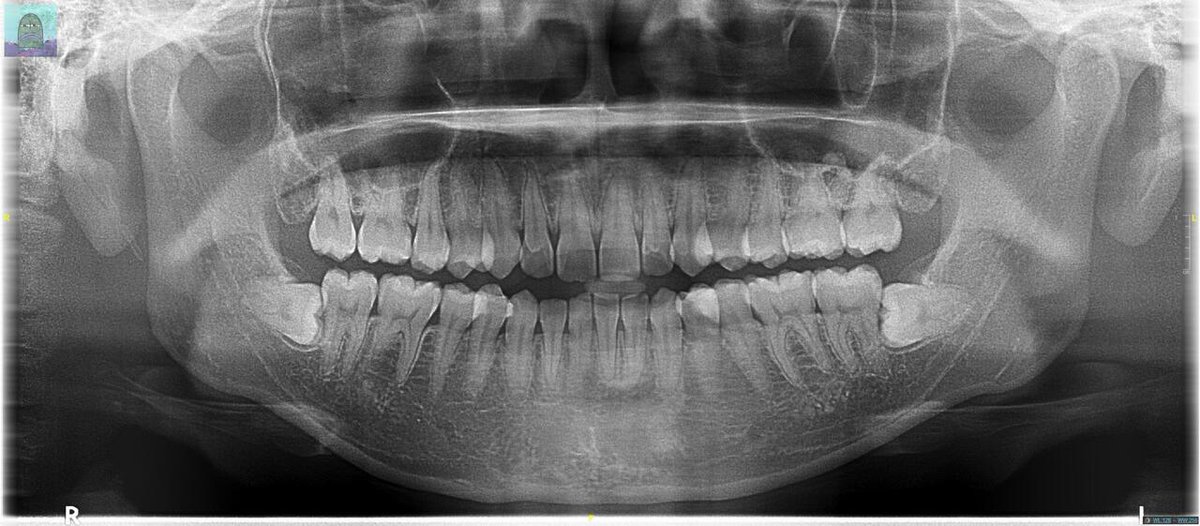

@tanyakanrl Itu nanti bisa jadi penyebab gigi sakit sih, mending dicabut. Cabut gigi bungu itu gratis pakai BPJS, tapi biasanya ngantri berbulan-bulan 🫠 Kalau mandiri, bisa langsung tapi bayar 3.5jtan 🥲 Gue pernah 2 gigi 6.8jt 😌